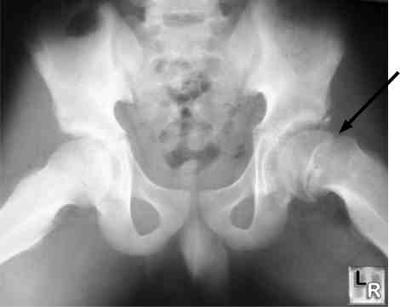

Fortunately you don't hip have hip dysplasia. The sockets, acetabulum, are normally formed and roofed, and the hips sit nicely in the sockets.

Your xray. Like I said too small, but I think I see small cam and pincer deformities of Femoro acetabular impingement syndrome in both hips.

Both may progress to osteoarthritis of the hip and I think on the hip on the reading left there may be some thinning of the cartilage.

You have really quite mild Femoro Acetabular Impingement syndrome and very early osteoarthritis in one of the hips. I can't tell which from the X-ray as they aren't marked. Hence your radiologist had little to say.